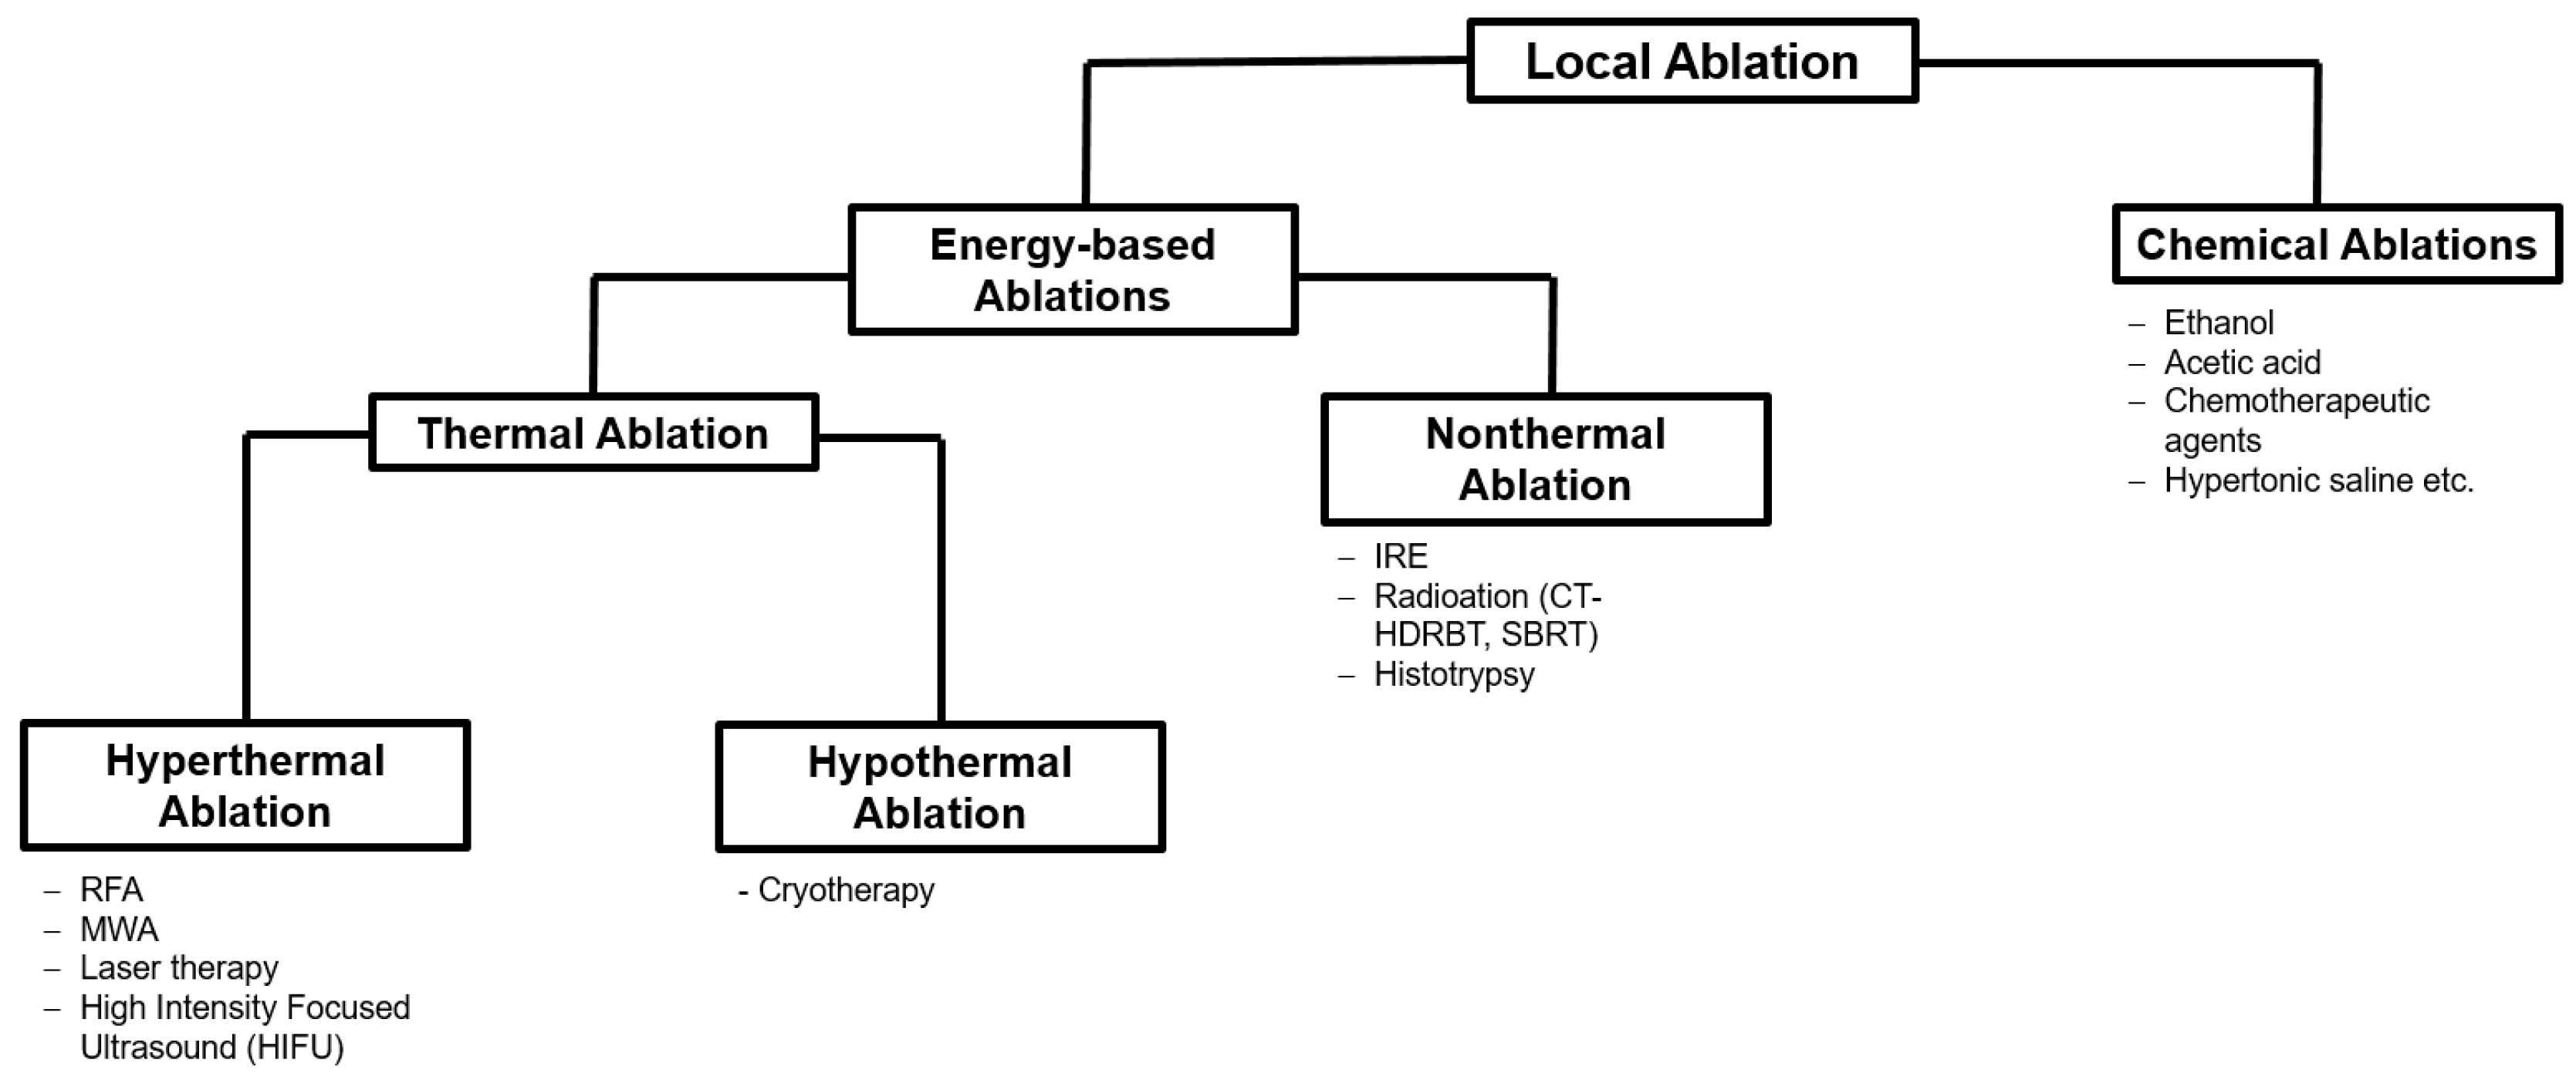

2. Ablation Procedures

2.1. Thermal Ablation

2.1.1. Radiofrequency Ablation (RFA)

2.1.2. Microwave Ablation (MWA)

2.1.3. Cryoablation

2.2. Non-Thermal Ablations

2.2.1. Computed Tomography High-Dose-Rate Brachytherapy (CT-HDRBT)

2.2.2. Irreversible Electroporation (IRE)